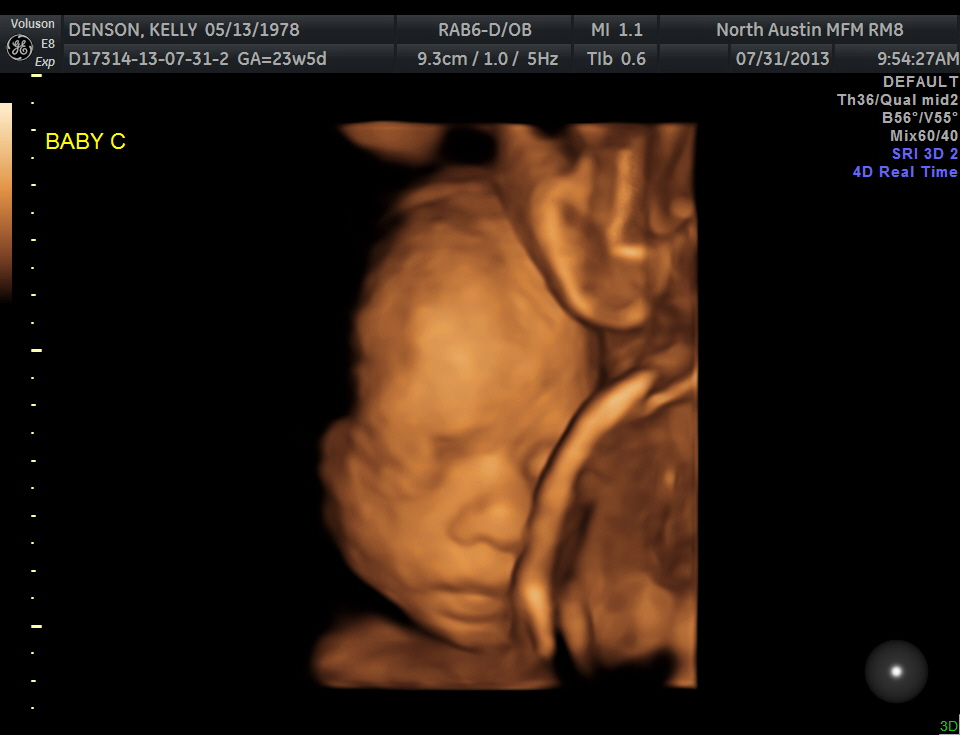

Ultrasound pics

Yesterday was my growth scan with Dr. Haeri. I'll do a second post with a full update in a minute-- first, here are the pics I got (on a CD, so better quality than the prints). C was the star of the show this week and poor Miss B got left out. But pretty neat to see some of the 3D images now!

Baby C:

Smiling:

How incredible is this??

Baby C is all over the place. Breech, then transverse, then head-down. He's a free spirit, or maybe just a camera hound, since he ended up positioning himself quite nicely for his 3D face pics. He's probably stayed the most consistent in growth percentiles, but that's now earned him a #2 spot in terms of absolute size. He is 1 lb., 6 ounces-- 37th percent in the growth percentiles and 92% of big brother A's weight.